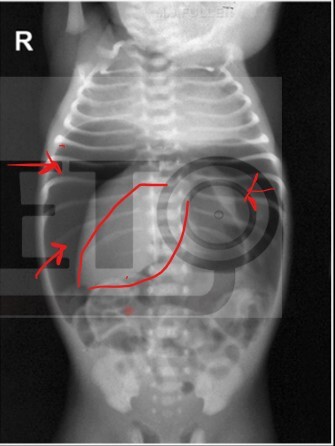

Segun los criterios de Bell . ¿ Que estadio comprende esta radiografia ?

llA = Caso confirmado , presencia de neumatosis en Radiografía Abdominal

Estadio de Enterocolitis Necrosante en este paciente

llB: presencia de cisuras y gas en sistema portal ( higado )